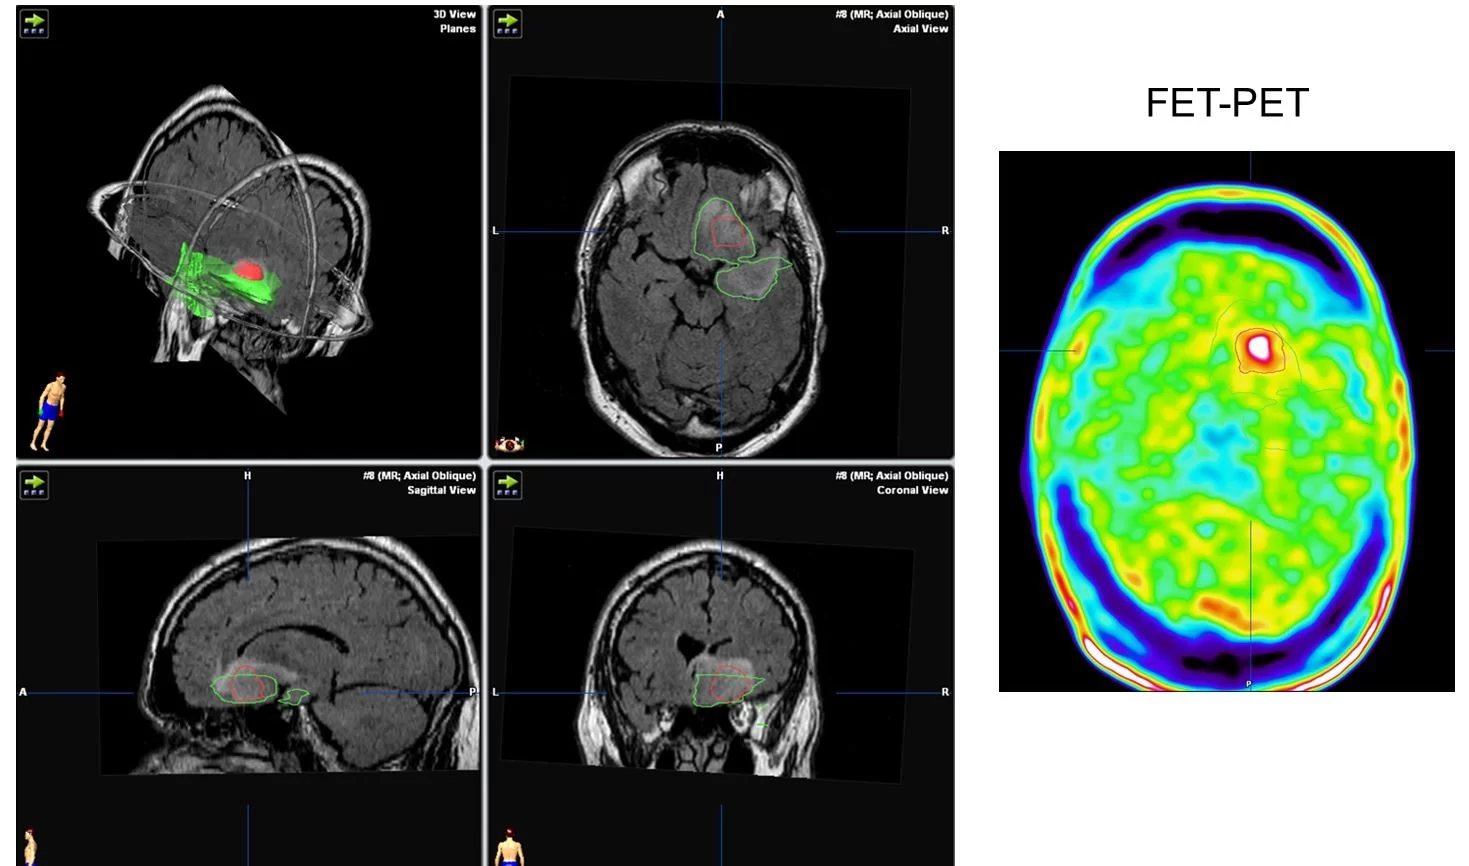

Σε πολλές περιπτώσεις ίσως χρειαστεί να γίνει μετά την αρχική διάγνωση, και μια πιο εξειδικευμένη μαγνητική τομογραφία, με ειδικές ακολουθίες (δηλαδή με τη λήψη ειδικών εικόνων) προκειμένω να προσδιοριστεί με μεγαλύτερη ακρίβεια για τι όγκο ακριβώς πρόκειται καθώς επίσης και το αν ο όγκος βρίσκεται κοντά σε ευαίσθητες περιοχές του εγκεφάλου. Μερικές φορές τα ευρήματα στη μαγνητική τομογραφία είναι αρκετά σαφή και η διάγνωση χαμηλόβαθμου γλοιώματος είναι αρκετά πιθανή. Ωστόσο, σχεδόν πάντα συνιστάται βιοψία για τον καθορισμό του τύπου του όγκου που υπάρχει.

Η βιοψία μπορεί να γίνει σε συνδυασμό με χειρουργική επέμβαση για την αφαίρεση του όγκου. Εναλλακτικά, ένα μικρό δείγμα μπορεί να αφαιρεθεί από τον όγκο με στερεοτακτικές τεχνικές, δηλαδή με την εισαγωγή μιας βελόνας στην ακριβή περιοχή του όγκου, χρησιμοποιώντας νευροπλοήγηση. Γενικά η στερεοτακτική βιοψία είναι ιδιαίτερα ασφαλής μέθοδος, με ποσοστό επιτυχίας περίπου 95%.

Χειρουργική αφαίρεση – Ο στόχος της χειρουργικής επέμβασης είναι η απομάκρυνση όσο το δυνατόν περισσότερου όγκου χωρίς βλάβη στον υγιή εγκέφαλο. Τα δεδομένα της σύγχρονης βιβλιογραφίας δείχνουν ότι η αφαίρεση της βλάβης, ακόμη και αν είναι υφολική (δηλ. αν δεν αφαιρεθεί ολόκληρος ο όγκος), έχει πλεονεκτήματα για την πρόγνωση. Όμως δεν είναι ακόμη σαφές πόσος όγκος πρέπει να αφαιρεθεί προκειμένω ο ασθενής να έχει σημαντικό όφελος από την επέμβαση.